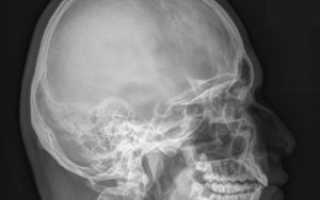

Костная структура черепа отличается высокой прочностью. Однако существуют ситуации, когда целостность такой структуры находится под угрозой. Рентген черепа порой является единственным методом аппаратной диагностики, способным выявить различного рода травмы, множественные заболевания, врожденные пороки.

Различные травмы и заболевания головы могут угрожать не только здоровью, но и жизни человека. Поэтому в большинстве случаев при возникновении патологических проявлений или травм назначается рентгенография костей черепа. Эта диагностическая процедура способна:

- выявить переломы свода черепа, лицевой части, нижней челюсти;

- обнаружить врожденные аномалии и пороки развития черепа;

- установить изменения костных структур;

- диагностировать синусит, гайморит;

- выявить остеопороз (разрушение костной ткани);

- помочь в исследовании пазух носа, турецкого седла, глазниц.

Стоит также понимать, для чего делают рентген черепа. Рентгенографию не делают для исследования мозга. Для этого врач отправит вас на различные виды томмографий, к примеру, МРТ или КТ. Причинами направления на рентген могут быть жалобы пациента или видимые клинические проявления (показания).

Как правило, рентген проводится в двух проекциях:

- прямой (фронтальной);

- боковой (сагиттальной).

На первом этапе пациента располагают таким образом, чтобы боковая поверхность его черепной коробки находилась параллельно функциональной поверхности, и делают снимок в сагиттальной проекции.

Центральный рентгеновский луч должен быть направлен на пару сантиметров выше прямой, соединяющей верхненаружный глазничный край с наружным слуховым проходом.

Если все сделано правильно, то на снимке клиновидные отростки, верхние стенки глазницы и наружные слуховые проходы будут накладываться друг на друга.

Качественно сделанный снимок в сагиттальной проекции позволяет специалисту изучить состояние как черепной коробки в целом, так и отдельных ее сегментов, в частности:

- черепных швов;

- турецкого седла;

- лицевого скелета;

- свода и основания.

На втором этапе делается фронтальный снимок головы пациента, для чего его располагают лицом вниз таким образом, чтобы сосцевидные отростки совпадали.

На фронтальном снимке врачу можно будет рассмотреть:

- венечный шов;

- чешую лобной кости;

- передние участки теменных костей.